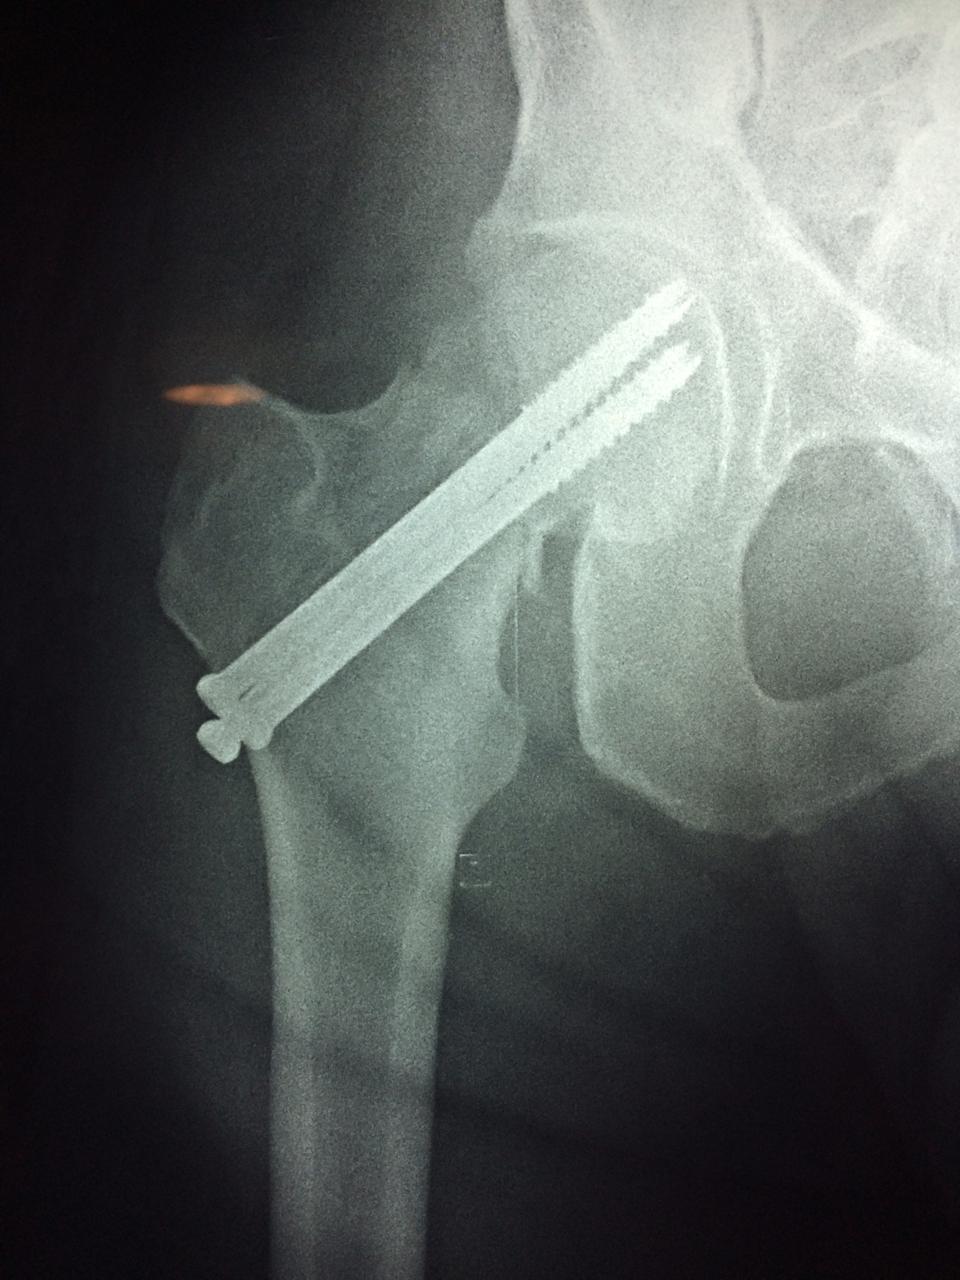

Cirugías de Cadera

La cirugía de fractura de cadera se realiza para reparar una ruptura en la parte superior del hueso del muslo. Este hueso se denomina fémur.

Es parte de la articulación coxofemoral. Si una fractura de cadera no recibe tratamiento, es posible que deba permanecer en una silla o en la cama.

A menudo se recomienda la cirugía para reparar la fractura debido a dichos riesgos.